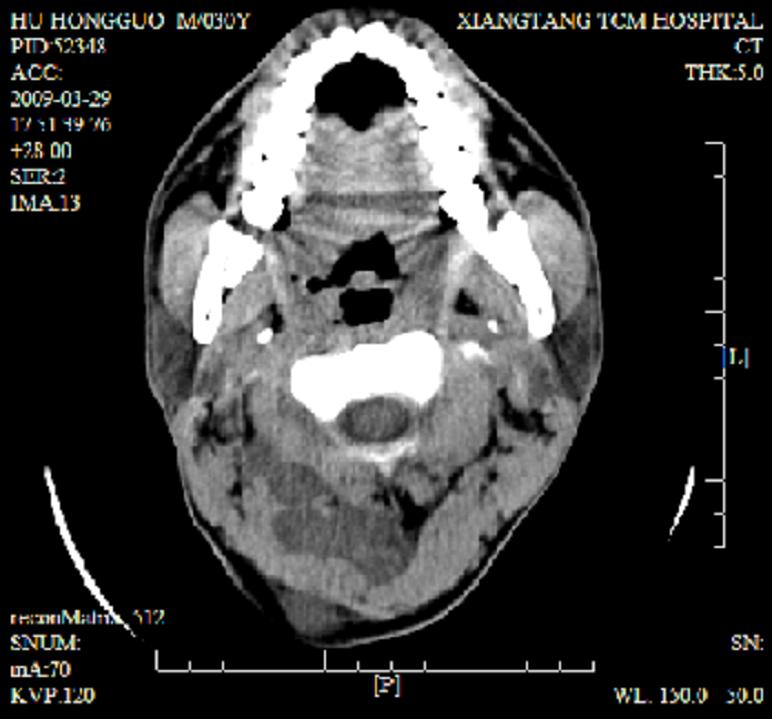

标题: CT19102:颈部肿块

男30y发现肿块3年

多处囊实性肿块,形态欠规则有一定形态,内见点状钙化,以囊变为主,增强后轻度强化,首先考虑神经源性肿瘤如鞘瘤,不除外脉管源性肿瘤如淋巴管瘤(见缝钻及囊性区域太多,如果合并感染完全可以这个影像表现),和海绵状血管瘤,但是血管瘤不太支持因为强化特征和病灶形态不典型.

右侧椎前间隙后部肌间、皮下囊性为主病变,可见分隔和点状钙化,分隔和壁呈轻度环形强化,大部分无强化。形态不规则,有钻缝特点。考虑1 淋巴管瘤合并感染2 血管平滑肌脂肪瘤3 表皮样囊肿4 不除外海绵状血管瘤。